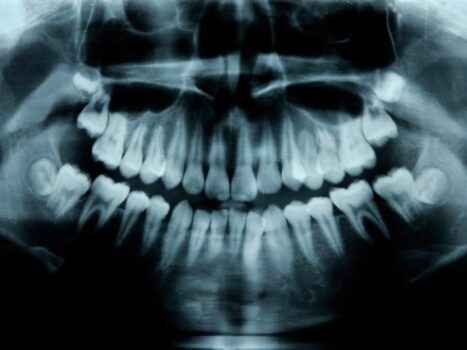

Cuidar tus dientes reduce el riesgo de muerte prematura

Diversos estudios muestran que las caries sin tratar y la pérdida de piezas aumentan el riesgo de enfermedades graves en la vejez.

Los restos humanos de la Antigüedad y la Edad Media ya han demostrado que la caries, los abscesos dentales y las inflamaciones cuyos efectos se extendían por todo el organismo solían implicar enfermedades graves e incluso la muerte mucho antes de que la odontología moderna desarrollara tratamientos eficaces. Incluso la Organización Mundial de la Salud reconoce el deterioro de la salud bucodental como un problema importante en las personas mayores. Cuando investigadores de la Universidad de Osaka, en Japón, revisaron los historiales médicos y dentales de casi 200.000 adultos de 75 años o más, descubrieron que quienes tenían más dientes perdidos o dañados confirmaban los resultados de un estudio previo que ya señalaba un mayor riesgo de mortalidad en comparación con quienes conservaban dientes sanos o empastados.

«El número de dientes es un indicador clave de la salud bucodental, ya que un bajo número de piezas existentes es un predictor de una amplia variedad de problemas de salud, como pérdida de peso, diabetes, hipertensión, enfermedades cardiovasculares, insuficiencia renal terminal, demencia, cáncer e incluso mortalidad», señalaron en un estudio publicado recientemente en la revista BMC Oral Health.

Otros trabajos respaldan esta afirmación. En Estados Unidos, la Encuesta Nacional de Salud y Nutrición (NHANES) sugiere que las personas con caries sin tratar —es decir, sin empastes ni otros tratamientos como coronas o endodoncias— presentan un mayor riesgo de mortalidad por cualquier causa, especialmente por enfermedades cardiovasculares. En un estudio realizado en Finlandia, los pacientes con enfermedad coronaria cuyas caries habían sido tratadas tenían muchas más probabilidades de vivir más tiempo que aquellos con caries que no habían recibido empastes. Lo que faltaba en los datos era un análisis que tuviera en cuenta tanto el número de dientes como su estado. Por eso, el equipo de Osaka decidió contabilizar las piezas dentales de los adultos mayores y evaluar su condición para estimar de forma más precisa el riesgo global de mortalidad.

Los dientes ya habían sido clasificados por dentistas que habían examinado previamente a los participantes como sanos, empastados o con caries, y posteriormente los investigadores hicieron un seguimiento de cada uno de ellos durante un periodo de 4 años. La probabilidad de mortalidad por cualquier causa mostró una fuerte asociación con el número total de dientes sanos y empastados, por encima de cualquier otra combinación de dientes sanos, empastados y con caries. La mayoría de los participantes que fallecieron antes de que concluyera el estudio o bien habían perdido dientes o sufrían caries. En cambio, se observó que quienes tenían todos los dientes sanos o sanos y empastados vivían más tiempo.

Otro estudio reciente, realizado por un equipo de investigación del Institute of Science Tokyo y publicado en la revista Geriatrics & Gerontology, analizó la relación entre la fragilidad oral y la mortalidad. La pérdida de dientes, la sequedad bucal, las dificultades para hablar y los problemas para masticar y tragar son algunos de los síntomas de la fragilidad oral. Los investigadores examinaron a algo más de 11.000 personas mayores que presentaban estos problemas y descubrieron que quienes tenían tres o más síntomas tenían 1,34 veces más probabilidades de morir durante el periodo del estudio. La fragilidad oral puede acortar la esperanza de vida debido a afecciones relacionadas con estos síntomas, como la desnutrición derivada de una masticación y deglución deficientes, que a su vez pueden provocar debilidad física. Las visitas al dentista añadieron aproximadamente un año de esperanza de vida saludable.

«El estado de fragilidad oral está significativamente asociado a una menor esperanza de vida saludable, lo que subraya la importancia de la salud bucodental en el bienestar de las personas mayores. Las visitas al dentista se asocian con una mayor esperanza de vida saludable en ambos sexos, independientemente del estado de fragilidad oral», señalaron los investigadores de Tokio.